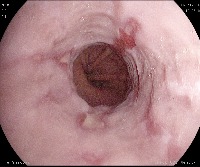

Overview This is the largest Gastrointestinal dataset generously provided by Simula Research Laboratory in Norway

In total, the dataset contains 10,662 labeled images stored using the JPEG format. The images can be found in the images folder. The classes, which each of the images belong to, correspond to the folder they are stored in (e.g., the ’polyp’ folder contains all polyp images, the ’barretts’ folder contains all images of Barrett’s esophagus, etc.). Each class-folder is located in a subfolder describing the type of finding, which again is located in a folder describing wheter it is a lower GI or upper GI finding. The number of images per class are not balanced, which is a general challenge in the medical field due to the fact that some findings occur more often than others. This adds an additional challenge for researchers, since methods applied to the data should also be able to learn from a small amount of training data. The labeled images represent 23 different classes of findings.

The data is collected during real gastro- and colonoscopy examinations at a Hospital in Norway and partly labeled by experienced gastrointestinal endoscopists.